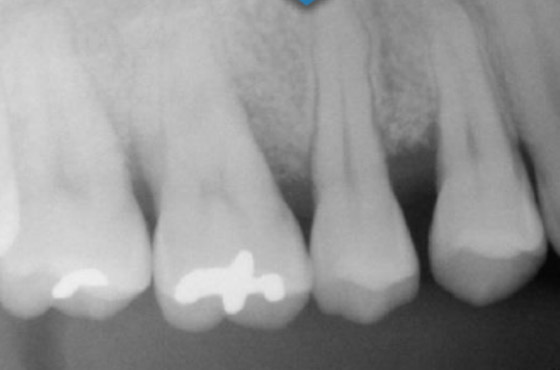

歯周病は、あごの骨を溶かす病気です。病状は歯肉の中で進行します。骨の様子を確認するため、当院では「CT」を使って検査します。

CTはレントゲンと同じくX線を用いた検査装置です。360度回転して撮影するので、あらゆる方向からの透過映像を立体的に確認でき、2次元のレントゲンより詳しく病状を把握できます。